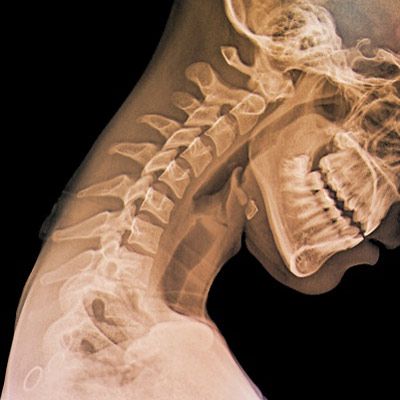

Что лучше делать для обследования позвоночника – рентген или МРТ

Рентгенография назначается для верификации изменений костных структур, легочной ткани, придаточных пазух носа. При травматических изменениях позвоночного столба рентген покажет переломы костных структур, смещение позвонков, наличие свободных фрагментов. Низкие экономические затраты и хорошая достоверность метода при изучении костно-суставной и легочной патологии делают метод незаменимым источником информации в травматологии, экстренной медицине.

Распространенные показания для выполнения рентгенографии:

- Травма спины, поясницы;

- Выявление пневмоний и туберкулеза легких;

- Повреждения челюсти и черепа.

При решении, рентген или мрт позвоночника – что лучше, следует указать на редкую применимость контрастных методик рентгеновского обследования спинного мозга. Внедрение в медицину МР-томографии постепенно вытеснило устаревшую технологию введения в спинномозговой канал омнипака, сопровождающуюся радиационным облучением, и имеющую более низкую достоверность (в сравнении с МРТ).